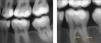

Comunicaciones interconductos: istmosLa configuración anatómica de los conductos radiculares nos presenta sistemas morfológicos complejos, incluyendo istmos entre ellos (fig. 12). La morfología y anchura vestibulolingual de la raíz mesial permite comunicaciones interconductos e istmos. En el momento actual, un istmo (anastomosis) se define como un pasaje que conecta dos o más conductos de la misma raíz61. En pacientes jóvenes, debemos esperar encontrar conductos grandes con istmos anchos (fig. 12c). Conforme se deposita dentina secundaria al ir madurando el diente, estas comunicaciones grandes se van dividiendo. Finalmente, su frecuencia disminuye después de los 40 años de edad62. Hsu y Kim63 clasificaron la configuración de los istmos, siendo la más frecuente la de tipo V entre las raíces mesiales de los molares inferiores. El tipo V se reconoce como una verdadera conexión o ancho corredor de tejido entre los dos conductos principales63. Después de revisar 1.615 primeros molares inferiores, la mitad de las raíces mesiales y un 20% de las raíces distales presentaban istmos de tipo V. Por lo tanto, cuando se tratan primeros molares inferiores, la presencia de istmos debe contemplarse más como norma que como excepción. Dada la extrema dificultad de desinfectar estos espacios inaccesibles64, nuestros esfuerzos se deben centrar en mejorar nuestros protocolos de irrigación con los diferentes sistemas disponibles hoy en día. La importancia clínica de reconocer, tratar, y desinfectar los istmos ha sido recientemente señalada por von Arx, quien identificó anastomosis cruzadas completas en un 29% de los casos fallidos que requieren cirugía apical65.

Raíces del primer molar inferior limpias en las que se puede observar una anastomosis cruzada. (a) Raíz mesial con tres conductos. Varias intercomunicaciones en el tercio medio entre los conductos mesiolingual y mesiocentral terminan combinándose. (b) Raíz distal con una anatomía compleja. Dos istmos tipo V, uno en el tercio medio y otro en el tercio apical. (c) Radiografía postoperatoria de un paciente de 14 años que demuestra la presencia de varios istmos y de comunicaciones interconductos.